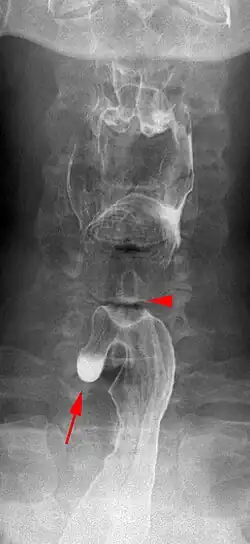

| Killian–Jamieson diverticulum. The arrowhead points at the closed upper esophageal sphincter, arrow points at the diverticulum partly filled with contrast medium. | |

A Killian–Jamieson diverticulum is an outpouching of the esophagus just below the upper esophageal sphincter.[1]

The physicians that first discovered the diverticulum were Gustav Killian and James Jamieson. Diverticula are seldom larger than 1.5 cm, and are less frequent than the similar Zenker's diverticula. As opposed to a Zenker's, which is typically a posterior and inferior outpouching from the esophagus, a Killian–Jamieson diverticulum is typically an anterolateral outpouching at the level of the C5-C6 vertebral bodies, due to a congenital weakness in the cervical esophagus between the oblique and transverse fibers of the cricopharyngeus muscle. It is usually smaller in size than a Zenker's diverticulum, and typically asymptomatic.[2] Although congenital, it is more commonly seen in elderly patients.[3]